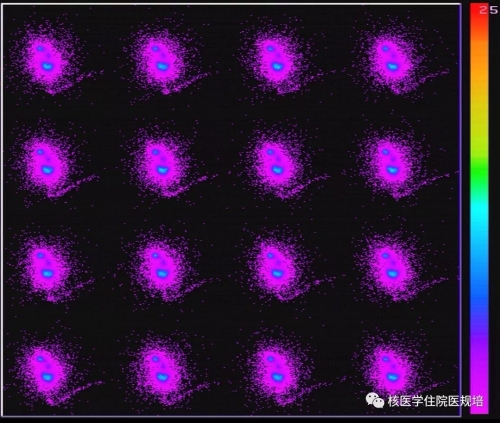

第1采集时相(60s):于第8s时可见左侧输卵管远端(卵巢)部位清晰显影,60s内右侧输卵管远端(卵巢)部位未见明显显影(图5)。

第2采集时相(30min):于1min时左侧输卵管远端(卵巢)部位清晰显影,2min时右侧输卵管远端(卵巢)部位见少量放射性聚集。延迟至60min时,子宫内可见少量放射性潴留(图6)。

第3采集时相:可见双侧输卵管远端(卵巢)及周围放射性聚集明显增加,弥散可(图7)。

检查意见:

左侧输卵管功能大致正常,右侧输卵管功能中度受损。